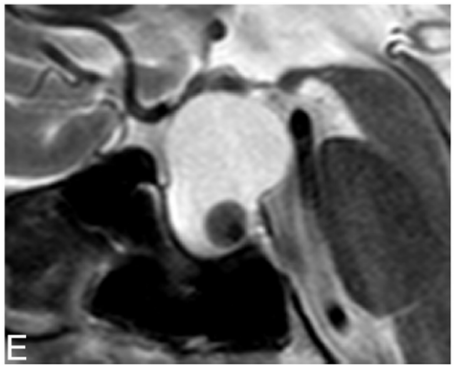

Uma mulher, 50 anos, assintomática, vem à consulta devido a

um achado na ressonância magnética de hipófise. Foi observada

uma imagem intrasselar, hiperintensa em T1 e T2, com nódulo

intracístico, conforme a imagem a seguir:

O diagnóstico mais provável e a conduta mais adequada para este caso são, respectivamente: